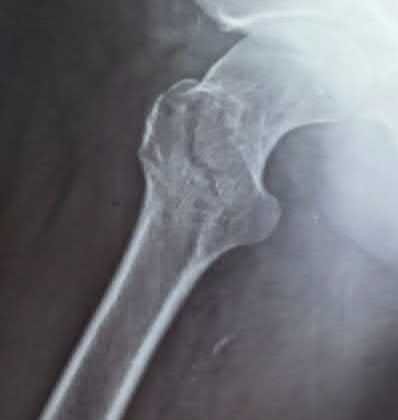

A 15-year-old boy presents with a permeative lytic lesion in the femoral diaphysis with aggressive periosteal reaction ('onion skinning'). Biopsy reveals uniform small round blue cells. Cytogenetic analysis of this tumor will most likely demonstrate which of the following translocations?

Explanation

The clinical and radiographic description is classic for Ewing sarcoma. The characteristic cytogenetic abnormality is a balanced translocation t(11;22)(q24;q12), which fuses the EWS gene on chromosome 22 with the FLI1 gene on chromosome 11. This is seen in approximately 85-90% of Ewing sarcomas. t(9;22) is the Philadelphia chromosome (CML), t(X;18) is seen in synovial sarcoma, t(2;13) in alveolar rhabdomyosarcoma, and t(12;16) in myxoid liposarcoma.